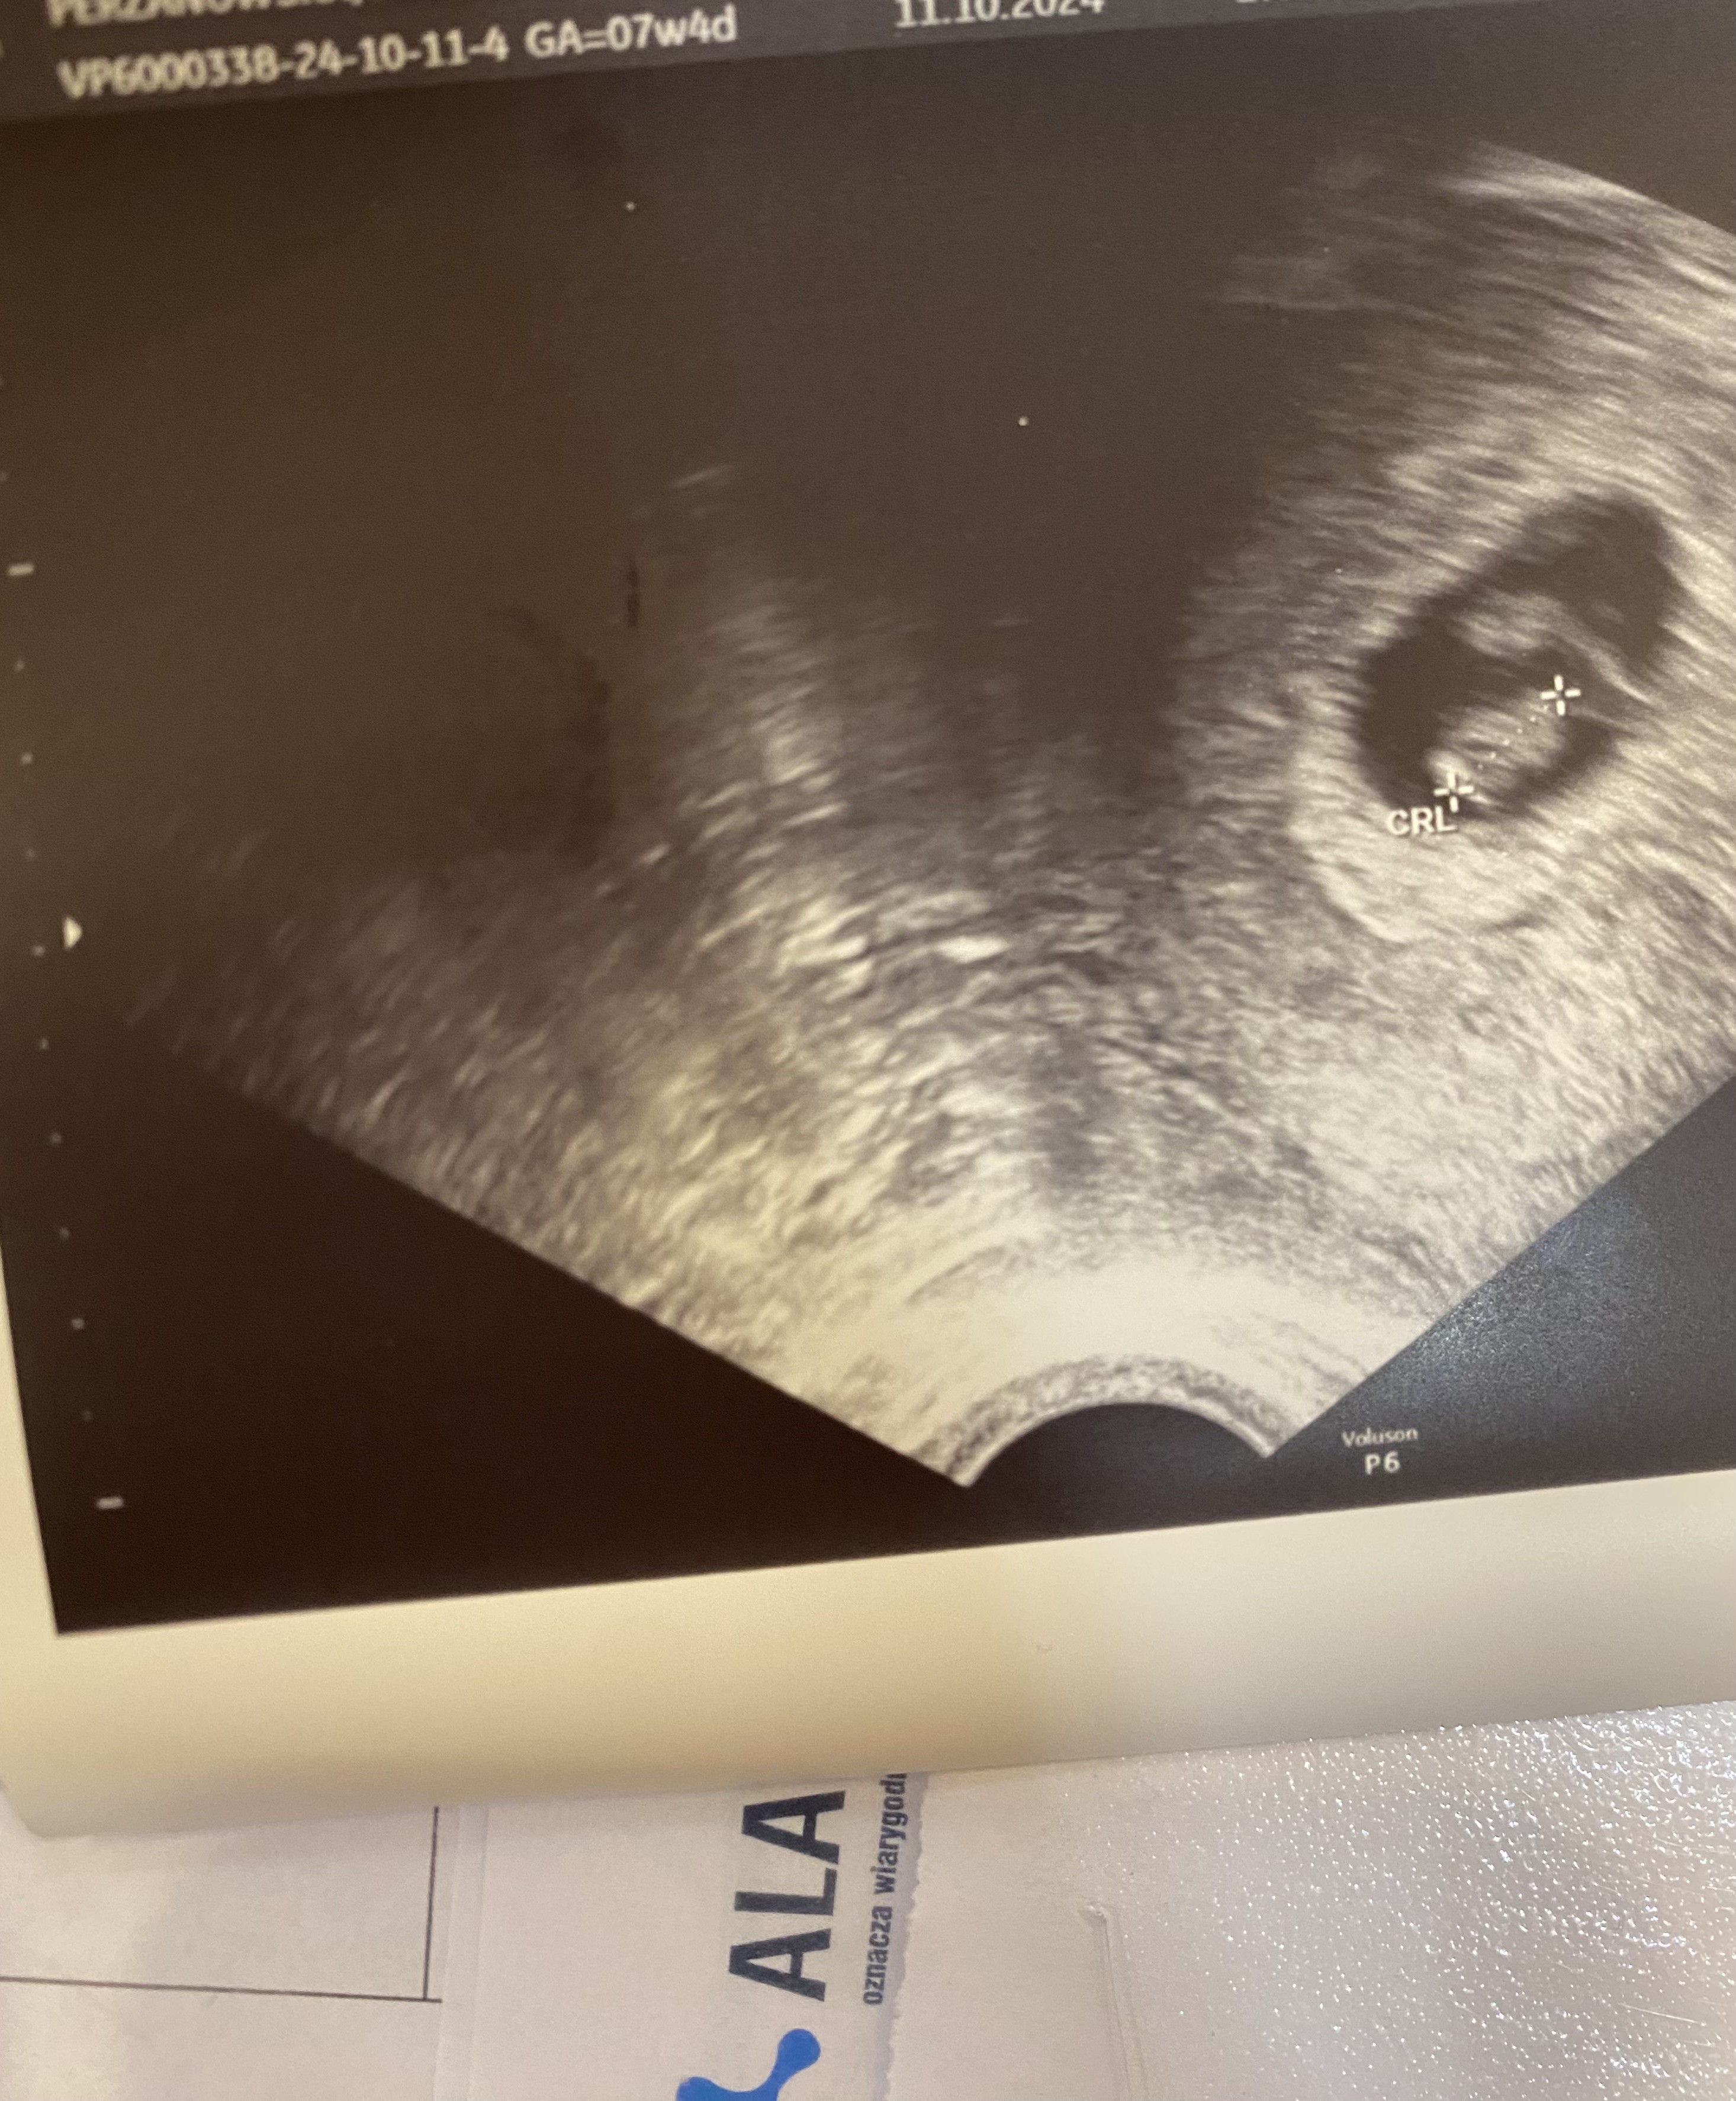

Hej dziewczyny, nasza jednocentymetrowa dzidzia pozdrawia ze 142 uderzeniami serduszka na minutę 🥹

Super, gratuluję 😊 Twój lekarz chyba ma fajne usg, bo ja dzisiaj liczyłam na trochę lepszy obraz, dzidzia prawie 2cm a na usg to tylko taka plamka 😁

Załączniki

• IMG-20241011-WA0009.jpeg

IMG-20241011-WA0009.jpeg

1,3 MB · Wyświetleń: 98

Gratulacje!!! Z tego co widzę, to u Ciebie tez spoko sprzęt, tylko chyba po prostu nie było przybliżenia 😅 u mnie jak najechała na jajniki to była jedna wielka plama, a mam obecnie 11 cm torbiel na jednym, wiec nie wiem, czy ten sprzęt rzeczywiście super 😅 ale serduszko i dzidzie było widać wyraźnie to najważniejsze :))